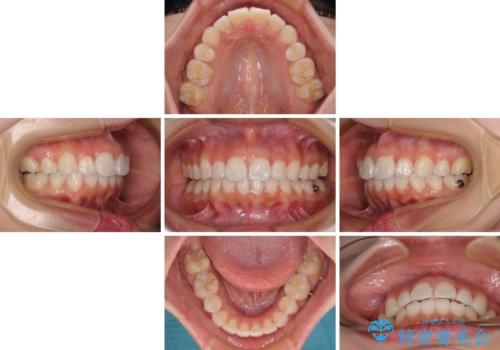

- 上下前歯の叢生を気にして来院された患者様です。

インビザラインでの治療を希望されていて、デコボコの程度が中等度であり、安価なパッケージにて対応可能と判断されたため、インビザライン・モデレートを用いて矯正治療を行うこととしました。